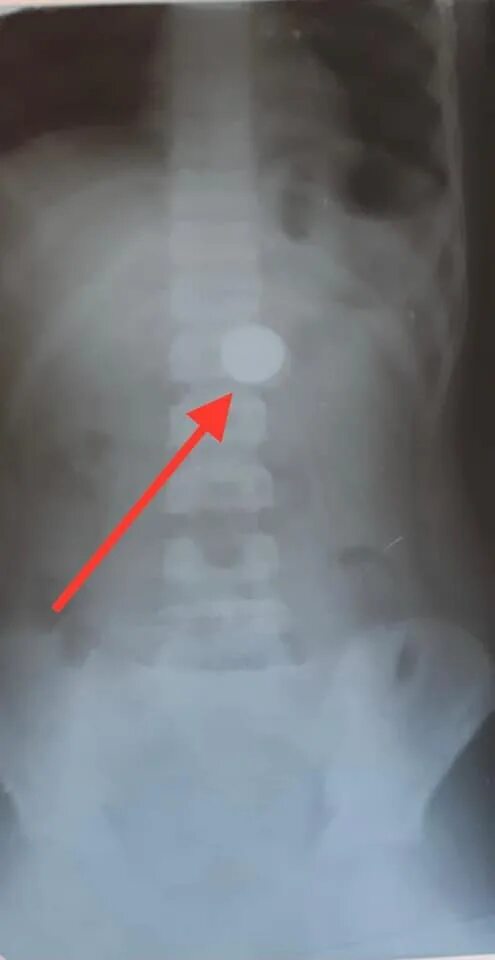

Что делать ребенку год проглотил монету